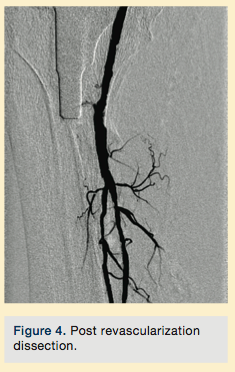

Peripheral angiography showed total occlusion of the right distal superficial femoral artery extending into the popliteal artery and into the trifurcation, with reconstitution of a peroneal and a posterior tibial. We attempted to obtain antegrade access to the lesions of the right infra-popliteal vessels (Figure 1). After failing to cross the lesion, we obtained retrograde access, puncturing from below the lesion through the posterior tibial artery near the ankle joint (Figure 2). Access was obtained and the lesion below the knee was crossed (Figure 3). Following this, the V-18 control wire (Boston Scientific) was snared from above, a CXI support catheter (CSI) was backloaded over the wire, and an antegrade Viperwire (CSI) was then placed, with removal of the retrograde sheath and wire. Atherectomy was performed with the 1.5mm Stealth 360° orbital atherectomy device (CSI) followed by balloon angioplasty with Cook, Sterling (Boston Scientific), and Chocolate (Cordis) balloon catheters. After angioplasty, significant improvement in luminal gain was noted at the expense of a dissection (Figure 4). We chose to place a Zilver PTX drug-eluting stent (Cook) within the distal superficial femoral and popliteal artery segment (Figure 5). After the procedure, the patient’s wounds completely healed. An angiogram 3 months later was performed, showing the vessels to be widely patent (Figure 6). The patient sent us a video of himself finally walking, and without pain (Video 1; online).